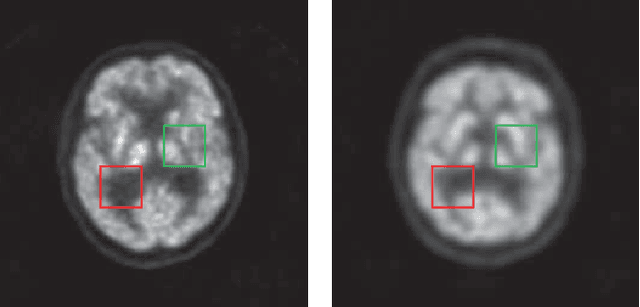

Abstract:Low resolution of positron emission tomography (PET) limits its diagnostic performance. Deep learning has been successfully applied to achieve super-resolution PET. However, commonly used supervised learning methods in this context require many pairs of low- and high-resolution (LR and HR) PET images. Although unsupervised learning utilizes unpaired images, the results are not as good as that obtained with supervised deep learning. In this paper, we propose a quasi-supervised learning method, which is a new type of weakly-supervised learning methods, to recover HR PET images from LR counterparts by leveraging similarity between unpaired LR and HR image patches. Specifically, LR image patches are taken from a patient as inputs, while the most similar HR patches from other patients are found as labels. The similarity between the matched HR and LR patches serves as a prior for network construction. Our proposed method can be implemented by designing a new network or modifying an existing network. As an example in this study, we have modified the cycle-consistent generative adversarial network (CycleGAN) for super-resolution PET. Our numerical and experimental results qualitatively and quantitatively show the merits of our method relative to the state-ofthe-art methods. The code is publicly available at https://github.com/PigYang-ops/CycleGAN-QSDL.